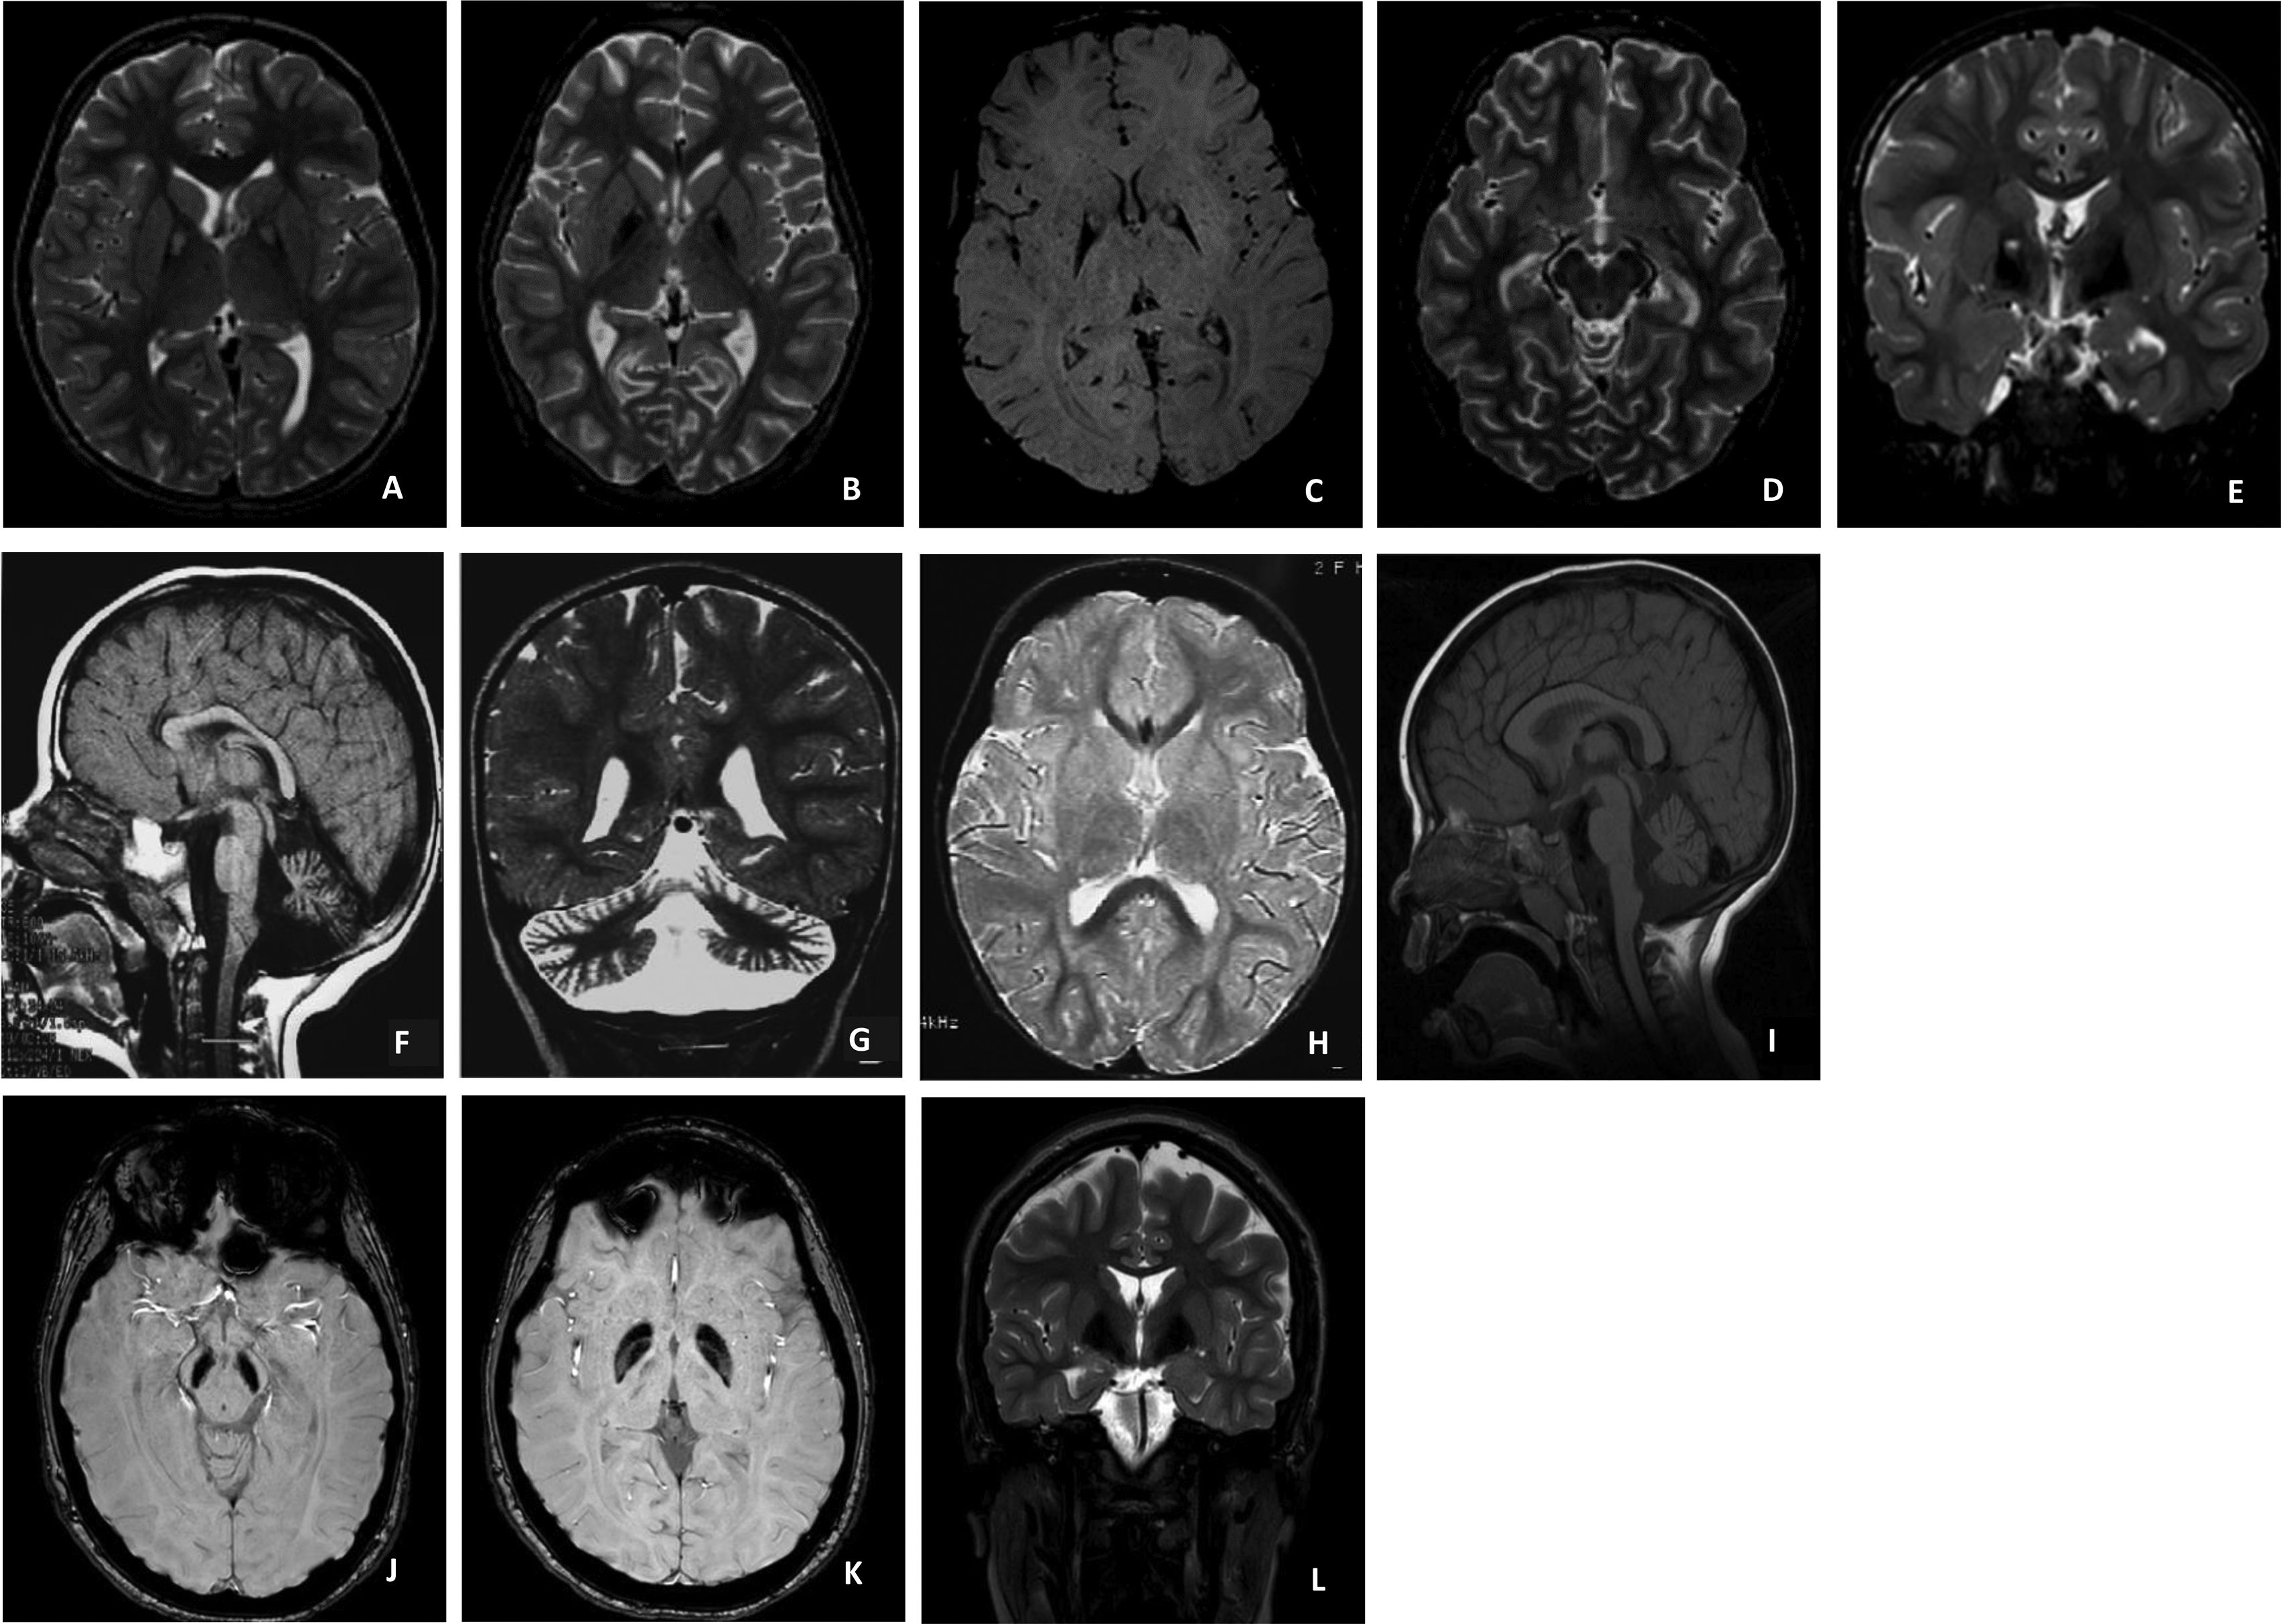

Neurodegeneration with brain iron accumulation: two decades of pediatric cases in a Portuguese Center

Background Neurodegeneration with brain iron accumulation (NBIA) comprises a group of rare and heterogeneous genetic disorders, in which early diagnosis can be challenging. Cases Retrospective review of clinical, neurophysiological, radiological, and molecular data from 18 […]